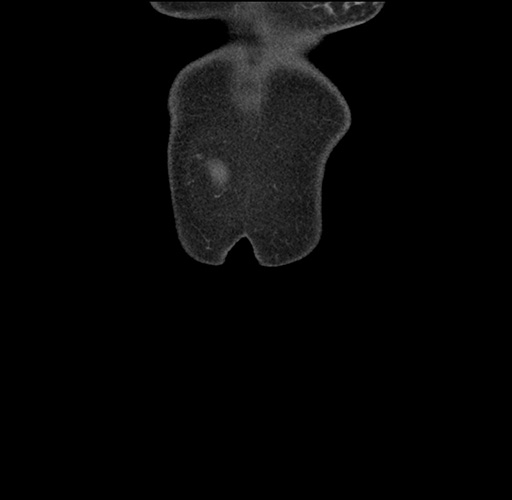

Imaging Analysis

Look through the patient's CT scan to identify any areas of concern for the necessary procedure.

Based on your CT findings, which issue(s) would give reason for "planned slowing down moment(s)" in this case?